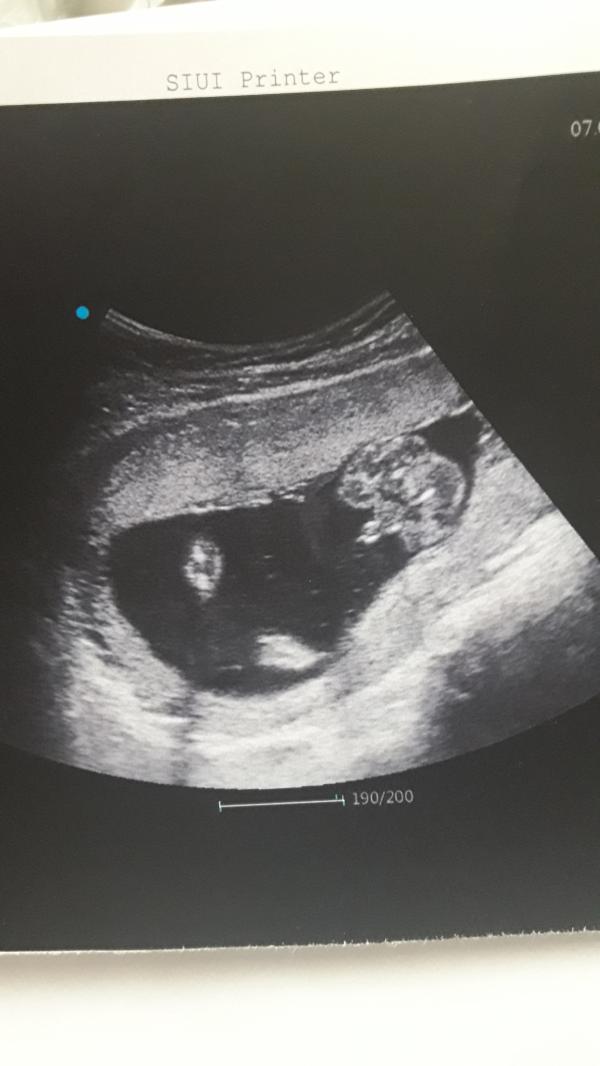

@s2209 они там так крутятся ) У меня пока узи делали он 2 раза с головы на попу перевернулся 😄

Где узи делали?